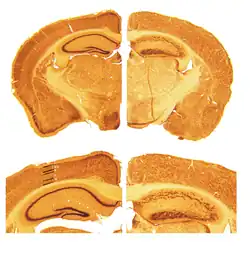

Brain slices of wildtype and reeler mice

Key pathological findings in the reeler brain structure